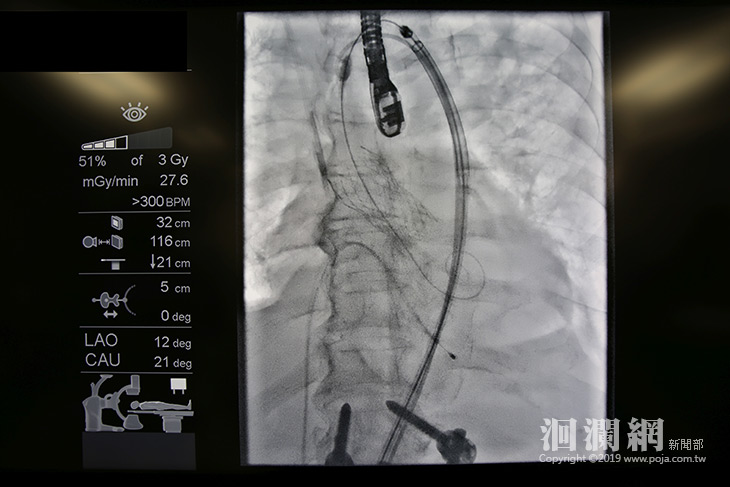

高階整合型手術室讓手術產生最大的不同,就在於手術室內建影像檢查系統,可以在手術中提供即時影像,達到更精準的手術治療。花蓮慈院外科部主任張睿智表示,高階整合型手術室在心臟治療的應用,更是能讓心臟內科及外科共同進行「經導管主動脈瓣膜置換術」,透過心導管的方式,就可以完成主動脈瓣膜置換,可說是比微創還要微創,適合應用在年紀較大等不適合開刀的病人。

因此花蓮慈濟醫院規畫建置東部第一間高階整合型手術室,讓心臟外科與內科可以攜手,共同進行經導管主動脈瓣膜置換術,利用心導管的技術,將無縫線的瓣膜送入主動脈與心臟的交接處進行置換,過程中不需要人工心肺機,甚至幾乎沒有傷口,出血量非常少,恢復期也更快,尤其是過程中不需要應用體外循環人工心肺機,更可以降低可能帶來的手術風險。

台上十分鐘,台下十年功。這句話也可以應用在「手術台」上。張睿智主任表示,對病人來說,經導管主動脈瓣膜置換術手術時間短、出血量小、恢復時間短;其實這也建立在醫療團隊要花更多時間與精力去準備,除了經過兩年的規劃,以許先生的手術為例,手術過程中有兩位具有十年以上心導管經驗與心律器的心臟內科醫師、兩位具有十年以上心臟血管手術經驗的心臟外科醫師、麻醉部醫護團隊、影像醫學部醫護團隊、手術室護理師與行政同仁共同努力。而且因為手術中使用影像醫學設備的關係,團隊還必須全程穿著約六公斤的鉛衣,張睿智主任說,這些努力就在看到病人與家屬的笑容後,一切都超級值得的!